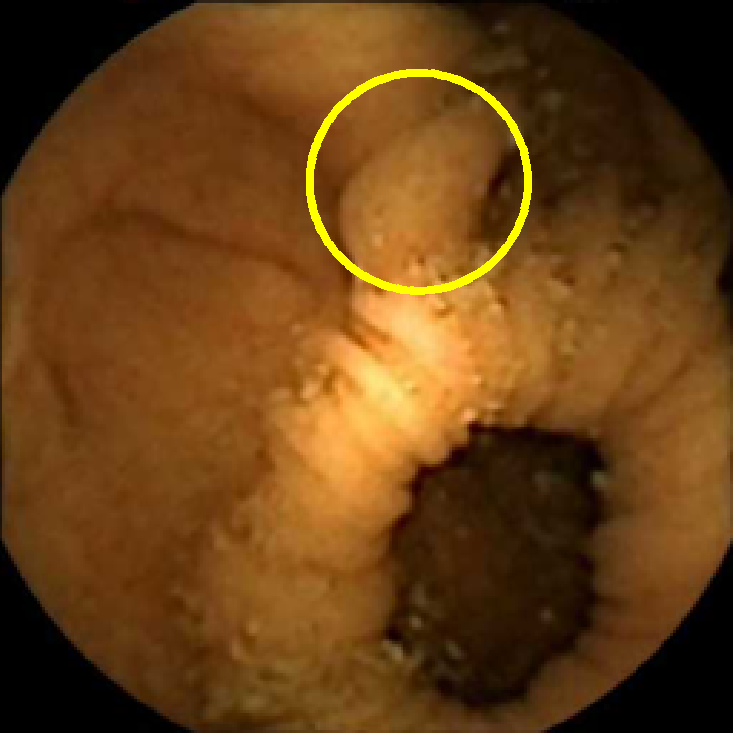

In Figure 5 we show the circles of radius corresponding to the features that were correctly classified as polyps by (29). We observe that the classifier was able to identify the polyps of a variety of shapes even in the presence of small amounts of trash liquid (first row) or when the polyps are located next to mucosal folds (rows two to four in column (c)).